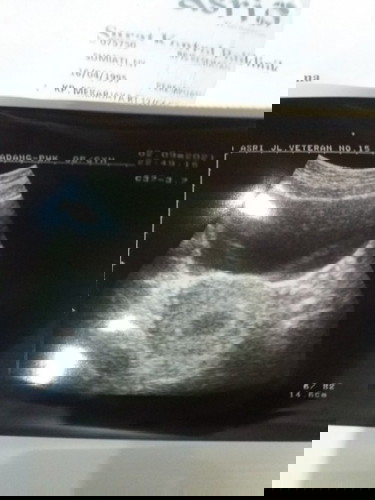

Dikira hamil 4 bulan ternyata baru 6 minggu itupun baru kantung kehamilan

Telat sampai 4 bulan sempat flek coklat 5 hari

ini lah Bun pentingnya USG di awal kehamilan,supaya ga terjadi seperti ini😊kalau sudah telat haid dan tespeck positif langsung USG biar perhitungan nya sama,kalau udh begini kan jdi bingung apa lg sebelumnya sempet flek,dibilang janin ngga berkembang pun kita gtw karena dri awal blm pernah usg,semoga aja EMG bner kandungannya msih 6 week ya Bun❤️dan semoga di usg selanjutnya sudah ada janinnya dan berkembang dengan sehat,doa yg terbaik utk bunda❤️🤗

kalo saya kehamilan 7mgg masih kantung aja yang membesar, disuruh nunggu bberapa minggu lagi😌 semoga kita semua diberikan kelancaran ya bunda ..